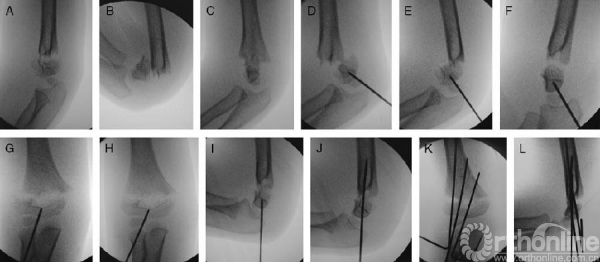

图2。一个5岁男孩的肱骨远端多向不稳定肱骨髁上骨折。A、多向不稳定骨折:伸直位时远折端分离及向后移动。B、在试图减小骨折移位后,远端骨折端已经先移动了。在病人术前准备及铺单之前就已经完成,因为该手术要求将病人手臂保持固定,C臂机环绕在肘关节周围。C.在轴向平面(旋转)中,这2个片段严重的移位。D、应用纵向牵引和操纵杆(2毫米)横向穿过未复位的肱骨小头。E.因为远端的片段是完全松动的,所以尝试用曲肘来取代之前的位置关系。F、轻轻转动肱骨近段直到获得一个完美的骨折远端侧面图像,操纵杆是用于在轴向平面旋转远端片段直到它在轴向平面(旋转)与近端片段对齐。注意,在矢状面骨折还未复位。G、C臂机在前后位(AP)旋转以发现骨折远端的横向位移。H.在冠状面上,可以通过轻轻的平移远端片段减小骨折移位。I.C臂机再次旋转到侧面。用操纵杆来纠正矢状面移位和远折端的成角畸形。J.在骨折复位后,操纵杆穿过骨折部位。K,另外两枚克氏针通过肱骨小头侧面穿入。L、C臂机拍摄正、侧位图像,最终确认骨折的解剖复位。

将C臂机放置在床的侧面,以便于在初始阶段纠正短缩和水平方向的旋转畸形。在已经应用纵向牵引并且骨折端没有恢复的情况下,肘关节屈曲大约90度,同时触诊明确骨折远折端的情况。在X线引导下,将一根2.0MM的克氏针经皮穿过肱骨小头。这枚克氏针将作为一个操纵杆提供骨折端解剖复位,在前后位(AP)视角下,它应该被放置在远端骨折片段横向的中间位置,并定位于中心或指向肱骨远端内侧柱。助手一只手稳稳抓住肱骨近端,而另一只手握住着手腕轻轻牵引并将肘部充分屈曲以便将骨折端完全对齐。(图1)轻轻转动肱骨近端段直至远端骨折端得到一个完美的侧面图像。操纵杆是用来在轴向平面旋转远侧片段的,直到它与近端片段对齐(图2)。应该得到部分恢复的肱骨远端外形的图象。在整个过程中,必须保持其近端片段稳定及保持不动,不需要进一步的动作。随着轴向平面(旋转)畸形的校正,C臂旋转到前后位置,通过推动内侧或外侧髁校正在冠状面上的任何移位。无论在内翻或外翻时,我们试图避免突然的移动,因为它可能与这种严重不稳定骨折在轴位和矢状位完全失去调整有关。一旦获得前后的对齐,C臂机旋转回侧面观。用操纵杆在伸展或屈曲位小心的操作远端片段直到矢状面畸形完全纠正。一旦完成复位,将操纵杆穿过骨折端近端以便进一步穿过内侧皮质。将第二及第三根克氏针用不同的方式插入,同时尽量让两根针远离彼此。在前后位,侧位及斜位等情况下,轻轻地在内翻外翻及内旋外旋时给与压力,以评估骨折复位程度及稳定性。将病人放在预先装好的中立位石膏托内,前臂屈肘约60度到70度。3-4周后,骨折愈合(骨膜反应及骨性愈合通过骨折部位),在下达相关医嘱后,于办公室经皮肤拔出克氏针。